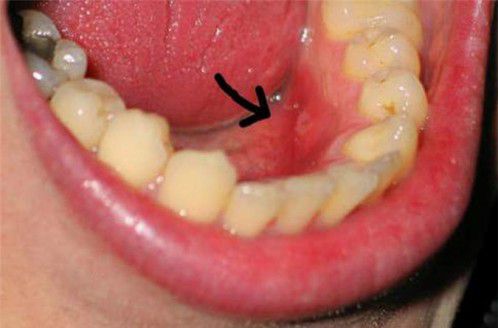

Click vào ảnh để xem 4 hình ảnh minh họa

Các hốc răng sẽ được làm ẩm bằng cách đắp gạc thuốc để loại bỏ các mảnh thức ăn bám ở đó. Thuốc giảm đau có thể được sử dụng.